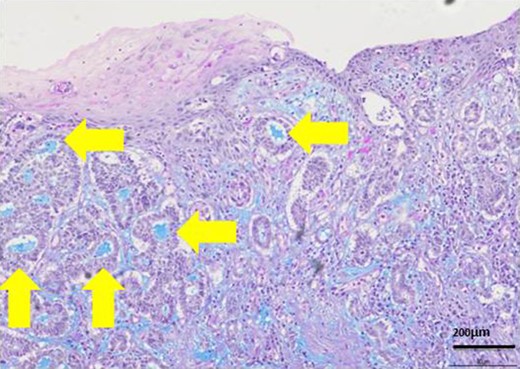

Most lumens had mucus which was stained blue by AL-B and PAS stain (yellow arrows). It showed lumens had acid mucopolysaccharide like sialomucin.